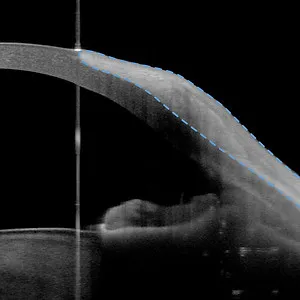

- OCT

- Vorderabschnitt-OCT (Anterion)